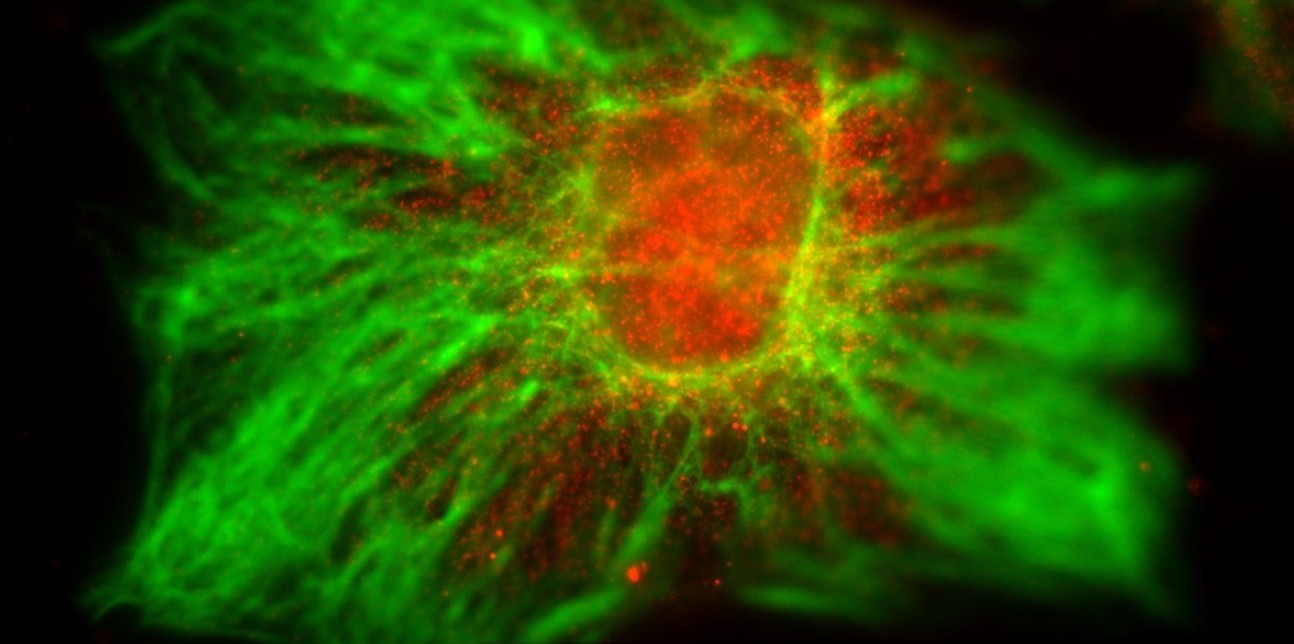

iPSC Derived Neural Stem Cells - Emma Mee-Hayes (Research Associate: Ye lab)

"iPSC Derived Neural Stem Cells. Stained for Nestin (Green) and Pax6 (Red)."